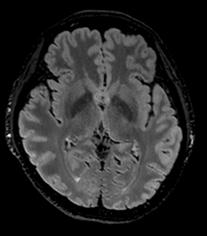

The power of MRI to pick up subtle injuries

Even the smallest injury in elite sports has implications. Having the right diagnostic tool at the peak of its development is vital to diagnosing subtle injuries that could impact player health. Using high resolution MRI therefore helps to identify very minute intra-articular joint injuries, muscle oedema changes or very small fibre tears (see fig 2).

Detailed diagnostic information is crucial to then accurately give the injury a grading using classification systems4 This grading severity then translates into an estimate of the mean number of player and training days that will be lost.

Although there is conflicting research about the value of using MRI to determine time out, undoubtedly having higher clinical confidence in injury analysis by using high clarity imaging outputs from new generation systems has the potential to be intrinsically linked to the rehabilitation and recovery time of the player. This, of course, also impacts long term asset performance and financial value.

Fig 2: Very small fibre tears identified using high resolution MRI